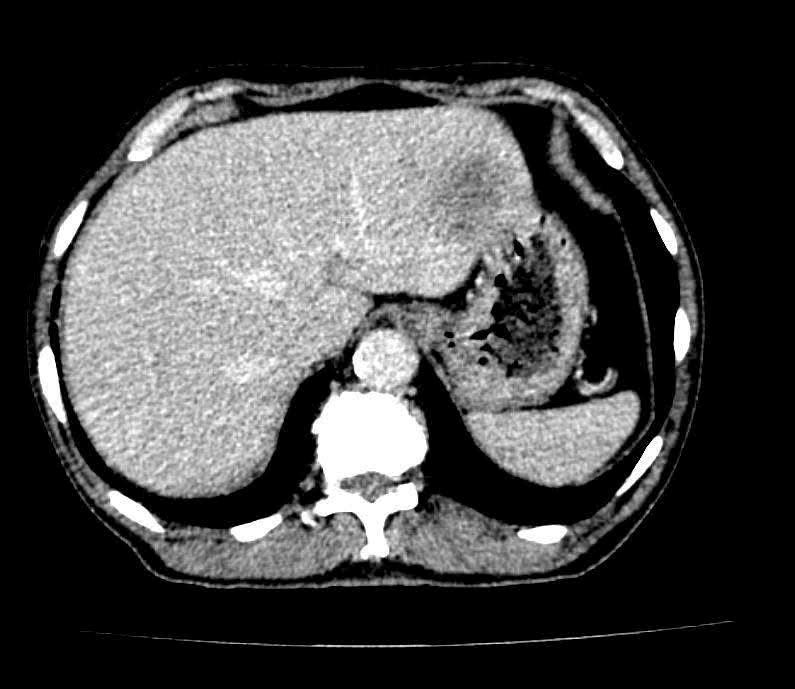

Nội soi tiêu hóa phát hiện tổn thương nghi ngờ ác tính. Các thăm dò hình ảnh tiếp theo ghi nhận tổn thương di căn gan, cho thấy bệnh đã ở giai đoạn tiến triển.

| Hình chụp của người bệnh khi khám sức khỏe tại bệnh viện. (Ảnh: BV198) |